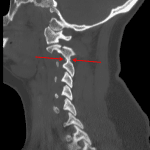

- Acute minimally displaced fracture extending through both C2 pedicles and through the posterior base of the odontoid process. The fracture extends into the lamina and C2-C3 facet joint on the left and into the transverse foramen on the right

- Perched left C2-C3 facet joint

- Focal kyphosis and mild anterolisthesis at C2-C3

- Thin ventral epidural hematoma at this level contributing to mild central stenosis

- Mild prevertebral edema

Acute minimally displaced fracture extending through the C2 pedicles and posterior aspect of the base of the odontoid process into the lamina and C2-C3 facet joint on the left and into the transverse foramen on the right. Associated x mm anterolisthesis of C2 on C3, focal kyphosis, and perched left C2-C3 facet joint, concerning for extensive ligamentous injury, which could be further assessed with MRI.

Thin x mm ventral epidural hematoma at this level, which in combination with the above described traumatic malalignment contributes to mild central stenosis. MRI could assess for cord injury.

Given traumatic malalignment and fracture extension into the transverse foramen on the right at C2-C3, neck CTA is recommended to assess for vascular injury.